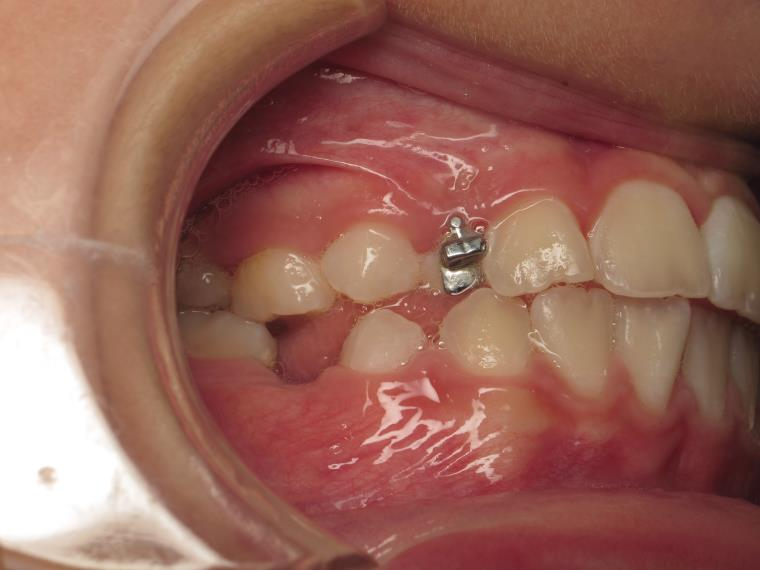

appareillage mobile pendant 9 mois

sectionnel multibagues pendant 25 mois